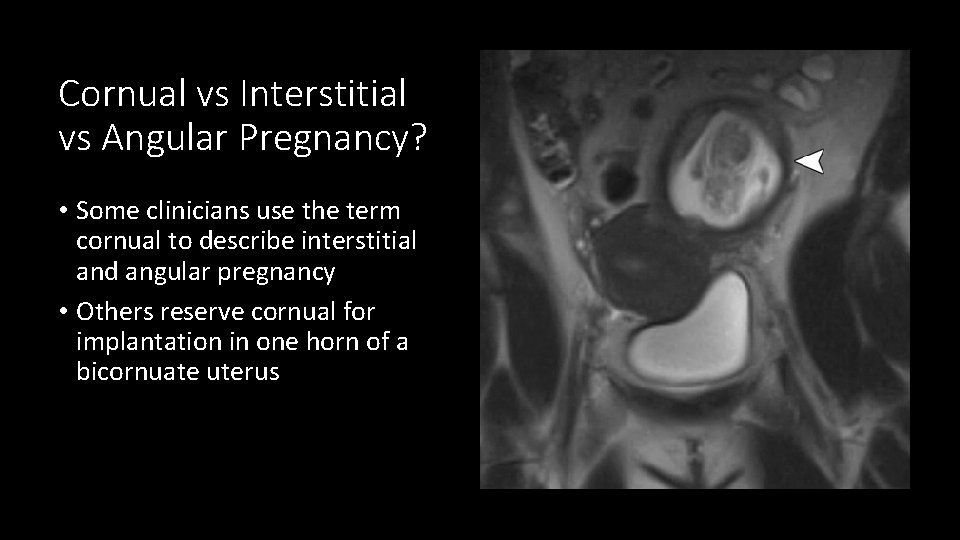

Cornual vs Interstitial vs Angular Pregnancy? • Some clinicians use the term cornual to describe interstitial and angular pregnancy • Others reserve cornual for implantation in one horn of a bicornuate uterus

Interstitial pregnancy • Implantation in the most proximal portion of the fallopian tube that traverses the myometrium • Important clinically because interstitial pregnancies have higher mortality than other ectopics • Surrounding myometrium can cause confusion for intrauterine pregnancy on US • Presence of surrounding myometrium has been postulated to allow for the pregnancies to be carried longer prior to presentation/rupture, although there is no good evidence to support this • Implantation is LATERAL to the uterine angle

Angular Pregnancy • Implantation in the lateral angle of the uterus, medial to the uterotubal junction • Completely surrounded by myometrium and can potentially be carried to term • However, high rates of rupture, placenta accreta and spontaneous loss • May present or rupture later in pregnancy